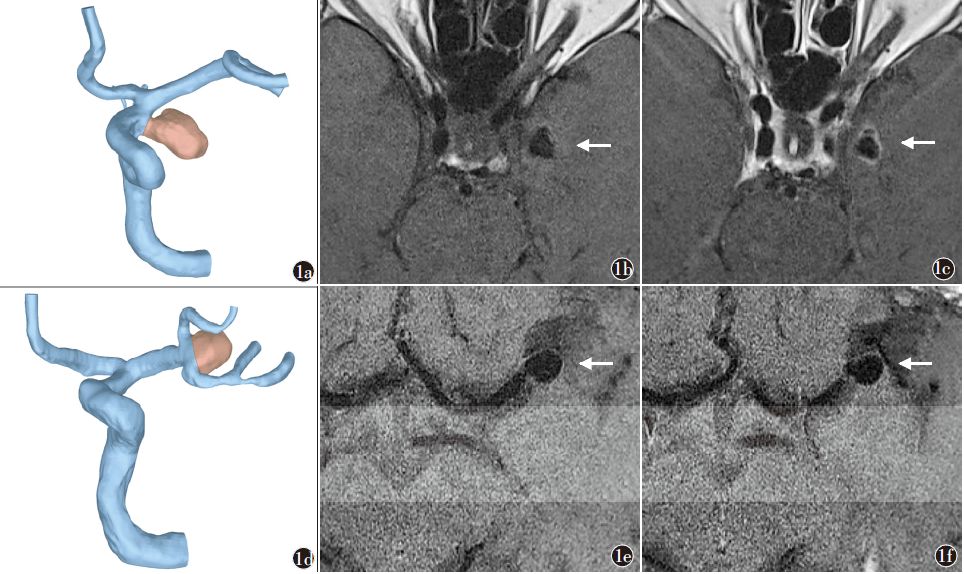

对于动脉瘤的破裂风险,另一个重要参数是“动脉瘤壁强化”,动脉瘤的变化主要是瘤壁,瘤壁的炎症是动脉瘤增长的真正动力;而高分辨MR可以直接观察动脉瘤壁强化程度,形态不稳定的(子囊形成型)表现为瘤壁强化。还有动脉瘤破裂风险量表(PHASES评分和ELAPSS评分)等参数。